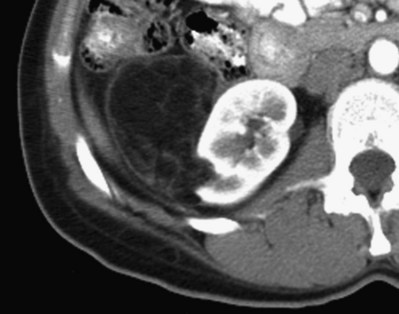

Radiologic appearance of MEST is of a complex cystic renal mass, typically classifying these tumors as Bosniak class III to IV lesions, indistinguishable from cystic RCC (Fig. 51–10A) (Adsay et al, 2000). A typical MEST has a benign clinical course, but recently a case of malignant transformation to a sarcomatoid carcinoma and several cases of local recurrence of a malignant stromal component with a dismal clinical course have been described (Adsay et al, 2000; Nakagawa et al, 2004).

Figure 51–10 Mixed epithelial and stromal tumor. A, CT scan characteristics are not distinguishable from renal cell carcinoma. B, Gross photograph of a partial nephrectomy specimen demonstrating a well-circumscribed mass composed of variably sized cysts separated by thick white septa. C, Medium-power magnification shows cysts lined by hobnailed cells and spindle cell stroma.